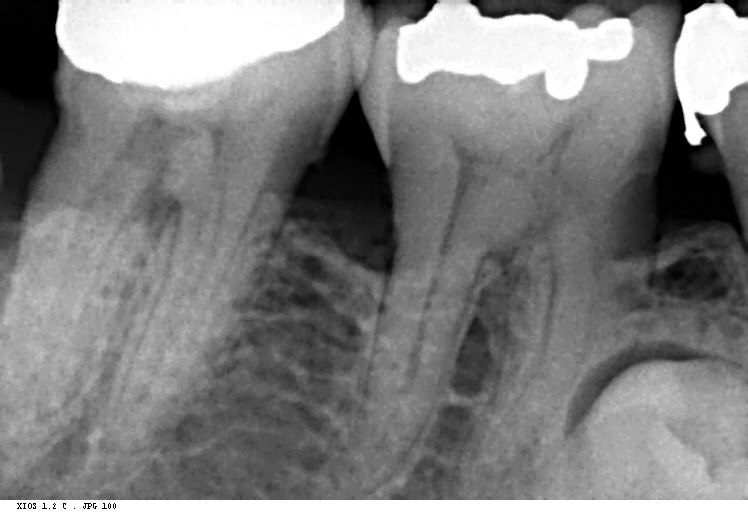

Question 1: What materials cannot be seen in the print of the X ray?

Question2: Which surface shows overhang?

Question 3: Which option is not evident on the print of the X ray?

Question 4: Which options cannot be seen in the print of the X ray?

Question 5: What options cannot be selected for tooth # 4.6?

Question 6: What options cannot be seen in the print of the X ray?

Question 7: What option cannot be identified on the print of the X ray?

Question 8: What condition can be seen in the X ray?

Question 9: Which option cannot be seen in the lower jaw?

Question 10: Which option can be selected for the following X ray?